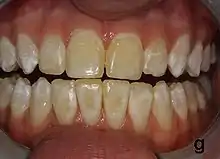

| Mild fluorosis: in its usual mildest form, fluorosis appears as opaque white patches on the enamel | |

It appears as a range of visual changes in enamel[4] causing degrees of intrinsic tooth discoloration, and, in some cases, physical damage to the teeth. The severity of the condition is dependent on the dose, duration, and age of the individual during the exposure.[1] The "very mild" (and most common) form of fluorosis, is characterized by small, opaque, "paper white” areas scattered irregularly over the tooth, covering less than 25% of the tooth surface. In the "mild" form of the disease, these mottled patches can involve up to half of the surface area of the teeth. When fluorosis is moderate, all of the surfaces of the teeth are mottled and teeth may be ground down and brown stains frequently "disfigure" the teeth. Severe fluorosis is characterized by brown discoloration and discrete or confluent pitting; brown stains are widespread and teeth often present a corroded-looking appearance.[1]